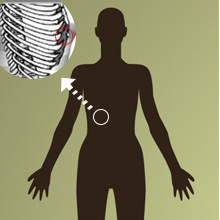

肋骨鼻尖立体

肋骨鼻尖立体乳房轮廓线下或第七肋软骨,切取所需长度,肋软骨有大量的来源,质地可靠,取材方法。适用于鼻整形各个部位。